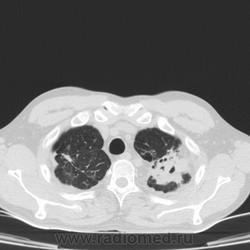

Больной туберкулезом со стажем болезни с 1996 ода, заболел по контакту с матерью. Все больные, заболевшие в 90е уже давно... Выявлен был с ИТЛ, потом диагноз поменялся на ФКТ, с 07 на цирротический. МЛУ не помню к каким препаратам. Периодическое бактериовыделение, каждый год выдает мбт+ микроскопией. Но в 12-13гг ни разу. Вот выцепила и сделала КТ, чтобы посмотреть- что же ТАМ у него осталось в легких. Чувствует себя отлично- курит, пьет, живет случайными заработками, инвалидность пожизненно

Классическая деформация легких. Никаких данных за активный ТВС нет, нет ничего, кроме кальцинатов. Слева - фиброзные и бронхоэктатические изменения+кальцинаты. Справа - чтой-то средней доли почти нет: неужто "с-м средней доли" постуб. генеза +кальцинаты? Ну пару булл есть. Но инвалидность все равно по функции будет оцениваться, не по изменениям в легких.

По данному КТ я бы оставил фиброзно-кавернозный туберкулёз (морфологически). Но фтизиатрам виднее.

Да он еще неплохо сохранился.